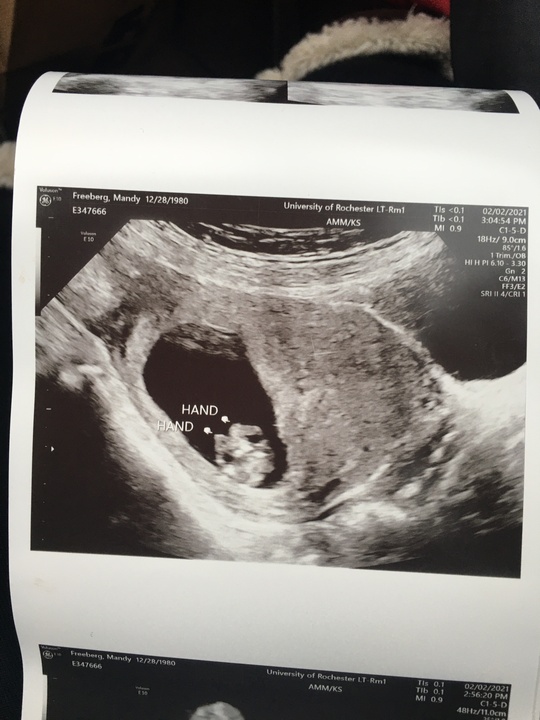

Amanda

February 6, 2021